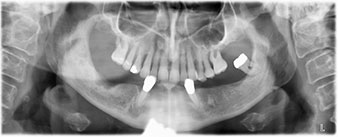

The 64-year-old patient presented with residual dentition of teeth 38, 33 and 43 and a clasp denture in the mandible (Fig. 1 and 2).

Following an explanation of the various treatment options open to her, the patient decided on extraction of the residual dentition in the mandible, an immediate implantation and treatment with the Fast & Fixed method (bredent medical), whereby the provisional fixed denture is screwed onto four implants on the same day as the surgery. The goal was to operate on the patient on the Friday so that she could assist in the oral examinations on the following Monday.

A three-dimensional cone beam computed tomography scan (CBCT, Planmeca) was performed to aid planning and minimize risks. This revealed that the quality and quantity of the available bone were sufficient for the surgery and immediate restoration using the Fast & Fixed method. Following the protocol for this concept, the implants are inserted at 35, 32, 42 and 45. Angling the distal implants by up to 45° shifts the emergence profile to posterior and generates a larger support polygon (Fig. 3).